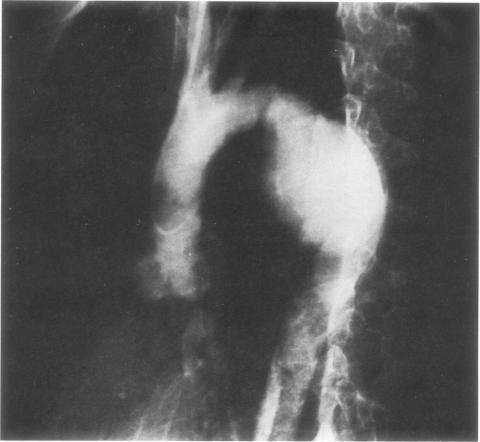

Between 1957 and 1983, 58 patients were treated in our institution for traumatic rupture of the thoracic aorta. Seven patients had acute ruptures and 51 had traumatic aneurysms. Surgical correction of the lesion was obtained by means of left femoral artery bypass in 17 patients, femoral artery-femoral vein bypass in five patients, and external shunt in three patients. After 1975, simple aortic cross-clamping was used in 33 patients. There was one death 1 week after a procedure for ventricular fibrillation. Paraplegia occurred in two patients, and both cases were correlated with hypotensive episodes. From this experience and that of others, it was determined that an aortogram should be performed in all patients suspected of having highspeed deceleration trauma, and that such patients should undergo surgical repair as soon as possible after diagnosis.

1957年至1983年间,我院共收治58例胸主动脉创伤性破裂患者。其中7例为急性破裂,51例为创伤性动脉瘤。17例患者通过左股动脉旁路手术进行病变的外科矫正,5例患者采用股动脉-股静脉旁路手术,3例患者采用体外分流术。1975年后,33例患者采用单纯主动脉交叉钳夹术。有1例患者在手术后1周因心室颤动死亡。2例患者发生截瘫,均与低血压发作有关。根据这一经验以及其他经验,确定所有怀疑有高速减速创伤的患者均应进行主动脉造影,且此类患者在诊断后应尽快接受手术修复。